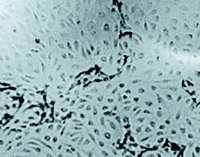

然后,我们通过培养的内皮细胞实验,从离体角度验证麝香保心丸的促血管生成效应,并初步探讨其作用机制。同样以bFGF和生理盐水为阳性和阴性对照,观察麝香保心丸药液对培养的牛肾上腺微血管内皮细胞增殖及管腔结构形成的影响,同时检测该药液作用下培养的人脐静脉内皮细胞血管内皮生长因子(VEGF)和bFGF的mRNA表达及其上清液中VEGF、bFGF含量。结果显示,保心丸组内皮细胞及管腔数目均较阴性对照组明显增多(保心丸大、小剂量组细胞数分别为1.31±0.19×105和1.19±0.22×105个/孔,管腔数分别为7.6±1.5和6.2±1.5个/10HP;阴性对照组细胞数为0.76±0.20×105个/孔,管腔数为3.3±0.7个/10HP。(HP指×100下的高倍视野,n=8)。保心丸组与阴性对照组之间细胞数与管腔数分别进行比较,均P<0.05),见图2。

图2 麝香保心丸对培养的牛肾上腺微血管内皮细胞管腔结构形成的影响

A:生理盐水对照组细胞

B:麝香保心丸组细胞

麝香保心丸组的细胞表达VEGF和bFGF mRNA明显增高,上清液中两因子含量明显增多(见图3)。表明麝香保心丸在体外的确具有促血管生成效应,其作用机制可能与促进内皮细胞释放VEGF、bFGF,并增高其mRNA表达有关。